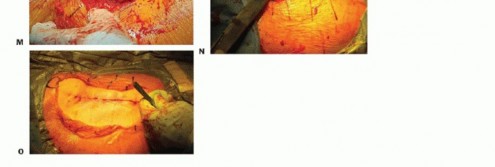

صورة طبية: نصف مفصل الورك: دليلك الشامل لدواعي الاستخدام والأنواع في صنعاء